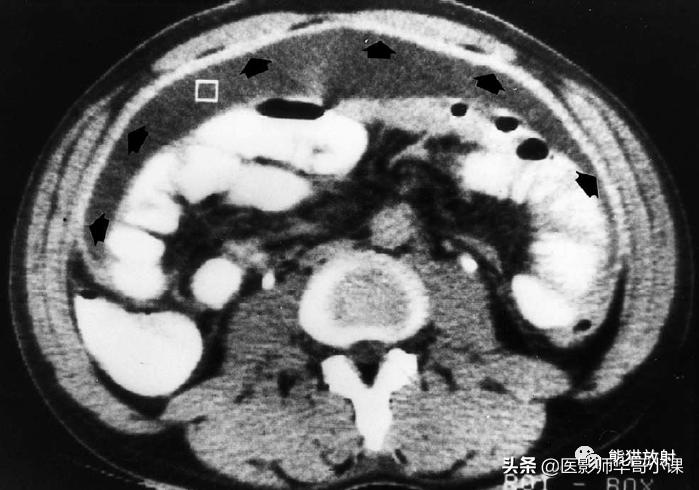

常见的表现 包括游离性或包裹性腹水,肠系膜血管束增粗,腹膜光滑均匀增厚和网膜被小而边界不清的软组织浸润(图)。CT上高CT值的腹水(20~45HU)反映了高蛋白质含量。

腹膜结核。CT显示明显增厚强化的壁层腹膜(黑箭)。注意高密度腹水(光标)